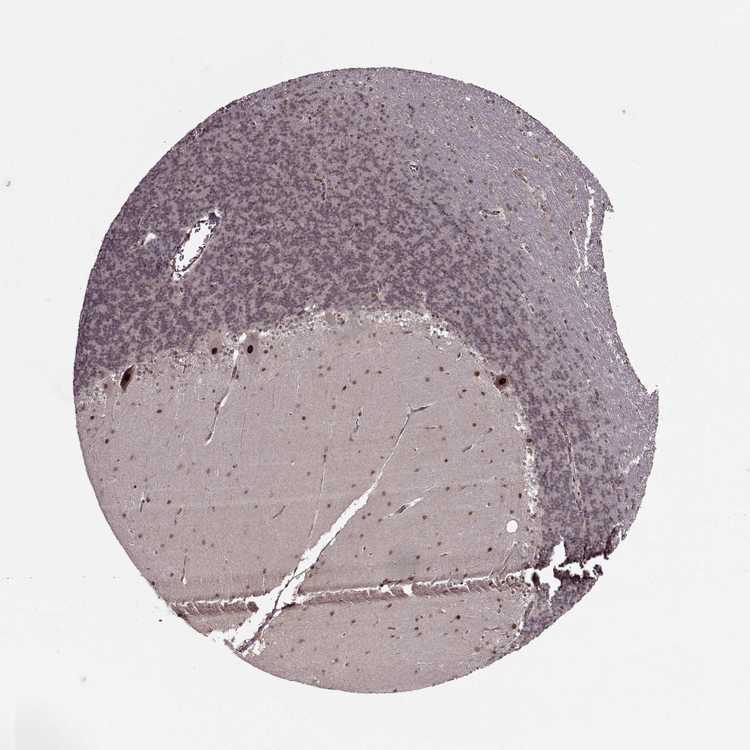

BRAIN CEREBELLUM Show tissue menu

CEREBELLUM - Expression summary

Protein expression

Cerebellumi

On the top, protein expression in current human tissue, based on all annotated cell types, is reported with the units not detected (n), low (l), medium (m) and high (h). Underneath, protein expression in each annotated cell type are reported using the same units.

Protein expression data is based on knowledge-based annotation. For genes where more than one antibody has been used, a collective score is set.

If knowledge-based annotation could not be performed for a gene, no data is displayed here. View antibody staining data further down this page.

Cells in granular layer: Low

Cells in molecular layer: Low

Purkinje cells: High

CEREBELLUM - Antibody stainingi

Antibody staining in the annotated cell types in the current human tissue is reported as not detected, low, medium, or high, based on conventional immunohistochemistry profiling in selected tissues. This score is based on the combination of the staining intensity and fraction of stained cells.

Each image is clickable and will lead to virtual microscopy that enables deeper exploration of all samples and also displays staining intensity scores, fraction scores and subcellular localization as well as patient and tissue information for each sample.

Antibody HPA047266Antibody CAB046007Antibody CAB046008

Purkinje cells MediumMediumHigh

Cells in granular layer Not detectedNot detectedLow

Cells in molecular layer Not detectedNot detectedLow